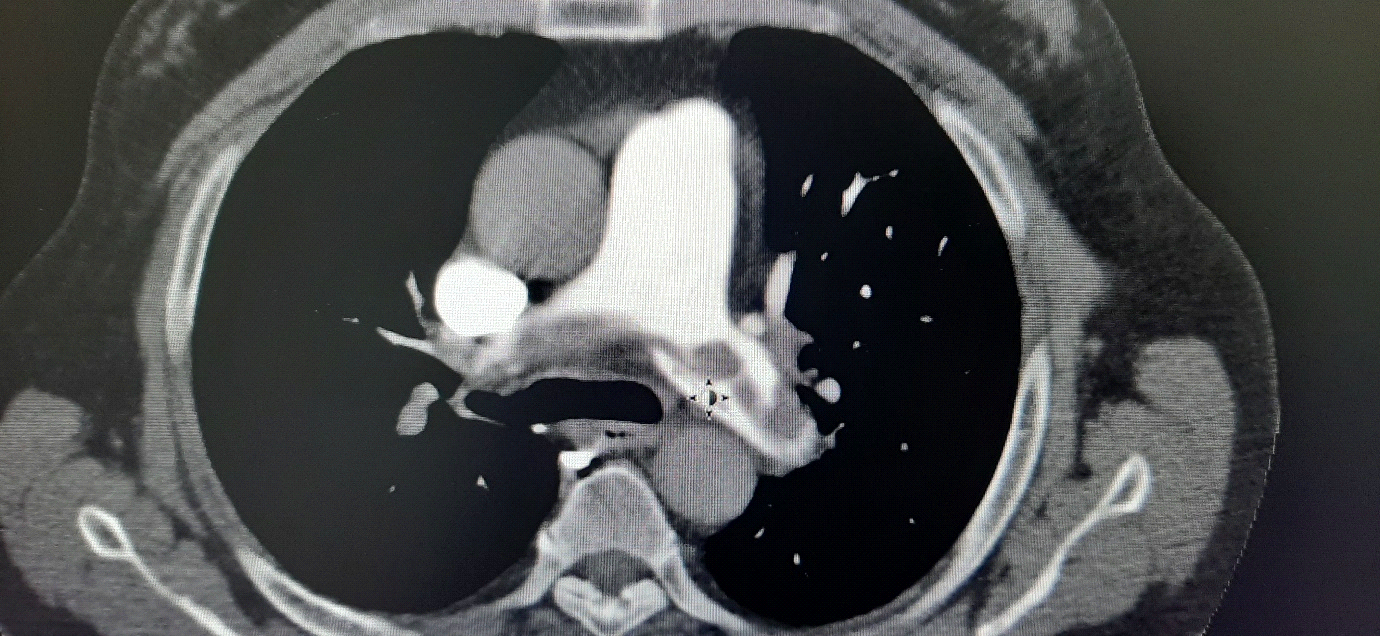

A 60 year old male admitted to emergency room presented with shortness of breath and easily fatigable. The patient is a known non-insulin dependent diabetic (NIDDM) and overweight. Following a work related knee injury 45 days prior to development of new symptoms the patient was diagnosed with meniscal and ACL tear using MRI. ECG shown in revealed a classic S1 Q3 T3. Transthoracic Echo was completed by Cardiologist colleague showing significant right ventricle dilatation and strain. The strongly suspected PE was confirmed by the significant elevated D Dimer and CTPA (Figure 1). An obvious extensive saddle shaped pulmonary artery (PA) embolism was detected at the bifurcation and extended to both right and left pulmonary arteries.

This 60 years old patient was admitted to ER in a state of highly suspected PE however he was in relatively stable condition. The diagnosis of PE was based on history of immobilization as a consequence of knee injury and the clinical picture of shortness of breath and tachycardia. ECG showed S1 Q3 T3 which occurs in 15 % of PE cases reflecting severe right heart strain and cor pulmonale.1 The right heart dilatation was confirmed by transthoracic echo. D-Dimer was significantly high and finally CT pulmonary angiogram (CTPA) demonstrated a large saddle embolus extending to both right and left pulmonary arteries.